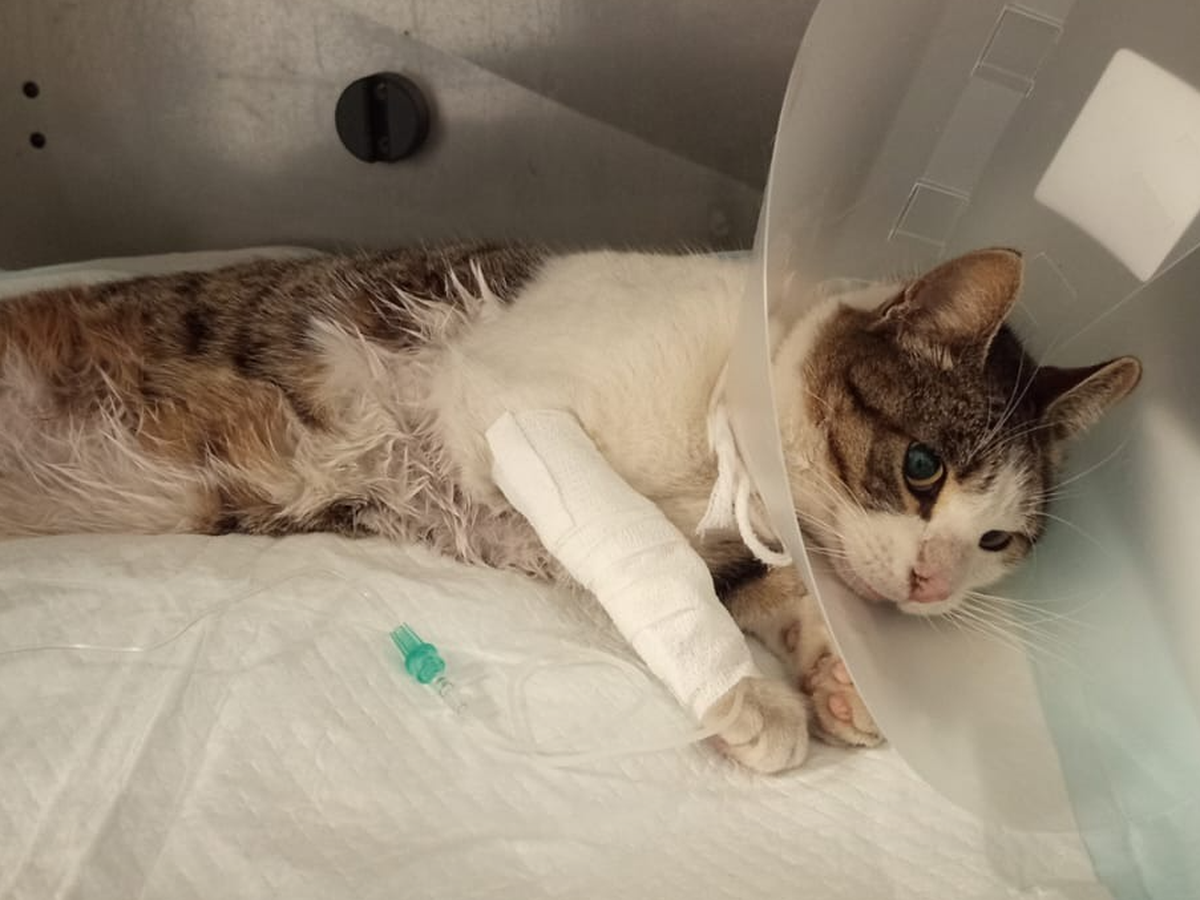

Il 6 gennaio riceviamo una chiamata dal signor Vincenzo Maniscalco: nel suo orto c’è un gatto che si trascina sul posteriore, incapace di camminare.

Quando arriviamo, Felice – perché così lo chiameremo – è nascosto in un ripostiglio, tremante, raggomitolato come un animale che ha smesso di credere nella bontà del mondo.

Ci vogliono più di due ore per prenderlo. Non fugge da noi: fugge dal dolore che qualcuno gli ha inflitto.

Al pronto soccorso veterinario di Milano, le radiografie parlano chiaro:

Felice ha un bossolo di proiettile vicino alla spina dorsale.

Un proiettile che è dentro di lui da tempo, perché le ferite esterne sono ormai cicatrizzate.

Qualcuno gli ha sparato.

Qualcuno ha preso la mira, ha premuto il grilletto e poi lo ha lasciato lì, a soffrire in silenzio.

Lo trasferiamo in un’altra clinica per una Risonanza Magnetica e ulteriori indagini.

Felice è affetto da FIP secca neurologica.

Da quel momento è seguito dal reparto di Neurologia, con cure continue e delicate.

E lui… lui reagisce.

Reagisce ai farmaci, reagisce alle terapie, reagisce alla vita.

E oggi, con nostra enorme emozione, Felice ha iniziato a mostrare reazioni agli arti inferiori.

Piccoli movimenti, piccoli segnali… ma per ora ci sono.

E per un gatto che non sentiva più nulla, è un miracolo.